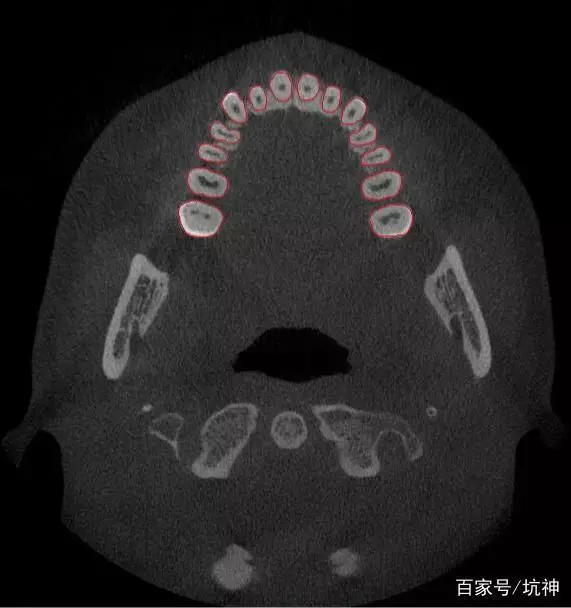

“Ortholink优领”个性化牙根功能△

它是通过机器的深度学习,用“机器判断+机器自动化操作”代替“主观判断+人工处理”,使用深度神经网络自动提取牙根数据、并完成牙根重建的一种智能化操作。

机器深度学习结果△

这项技术大大解放了劳动力,处理效率提高了300%,而且处理结果的精度更高,初步实现了人工到人工智能的转变!当人工智能概念与数字化正畸技术相融合,数字化技术便能从人的角度出发,想人之所想,让智慧化的正畸成为可能。